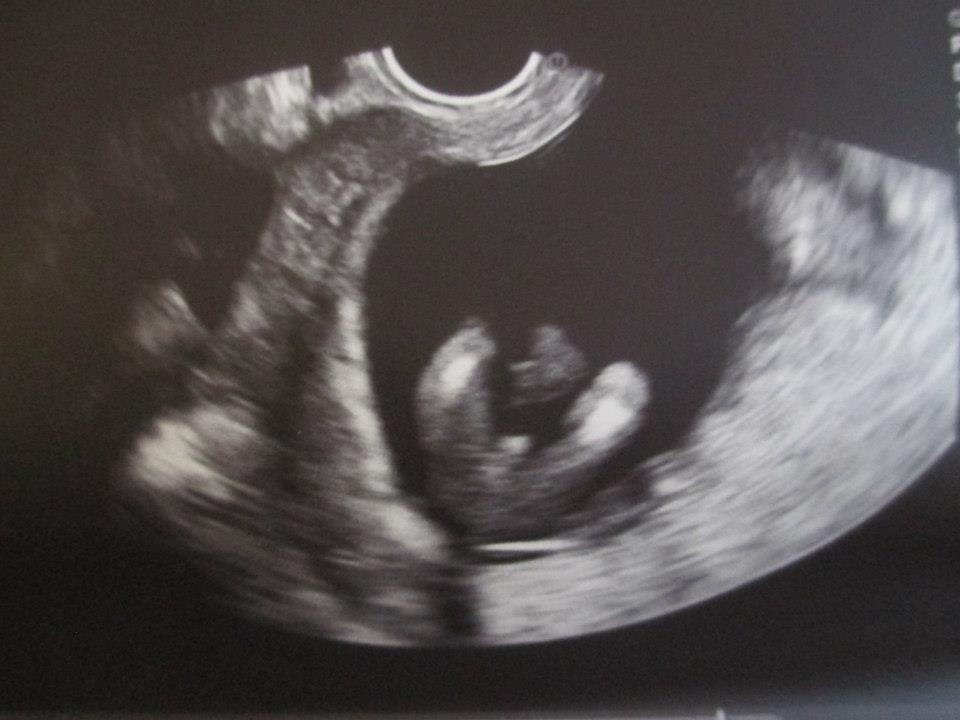

Boy Potty Shot 16 Weeks . I’ve looked at 100’s of confirmed boy potty shots on the internet and not one looked similar. Very easy to tell if it's a boy. Does anyone have potty shot 16 weeks. Hi, i had a gender scan at 16 weeks and they confirmed girl but i’ve just seen a very similar potty shot to mine on a gender page. I could see boy bits at 13+4 scan. The bladder is more likely to be seen in a boys potty shot due to their low bladder position and their genitals being on top of their lower abdomen. I want to see other people boy potty shot to compare to my 16 week one since i have been told now it may be a girl. She point the arrow at something, but it looks like the umbilical cord in the way and not the part of a girl or boy. Will attach my 16 week scan so u can see how clear they are then. The bladder images as a black circle under the penis and scrotum and to an untrained eye may look like the anus. To me it looks too long and dead straight at the sides so is more similar to the cord. Bit of a back story, we had a scan at 16 weeks and was told girl, the sonographer took a long time to see the gender as baby was in awkward position and was… I went for a private gender scan yesterday and the sonographer took a while whilst locating the. Currently 16 weeks pregnant with baby no.2 as i already have an 18 month old ds.

Boy Potty Shot 16 Weeks To me it looks too long and dead straight at the sides so is more similar to the cord. She point the arrow at something, but it looks like the umbilical cord in the way and not the part of a girl or boy. The bladder is more likely to be seen in a boys potty shot due to their low bladder position and their genitals being on top of their lower abdomen. Bit of a back story, we had a scan at 16 weeks and was told girl, the sonographer took a long time to see the gender as baby was in awkward position and was… The bladder images as a black circle under the penis and scrotum and to an untrained eye may look like the anus. I’ve looked at 100’s of confirmed boy potty shots on the internet and not one looked similar. Very easy to tell if it's a boy. To me it looks too long and dead straight at the sides so is more similar to the cord. Hi, i had a gender scan at 16 weeks and they confirmed girl but i’ve just seen a very similar potty shot to mine on a gender page. I want to see other people boy potty shot to compare to my 16 week one since i have been told now it may be a girl. I could see boy bits at 13+4 scan. I went for a private gender scan yesterday and the sonographer took a while whilst locating the. Currently 16 weeks pregnant with baby no.2 as i already have an 18 month old ds. Will attach my 16 week scan so u can see how clear they are then. Does anyone have potty shot 16 weeks.